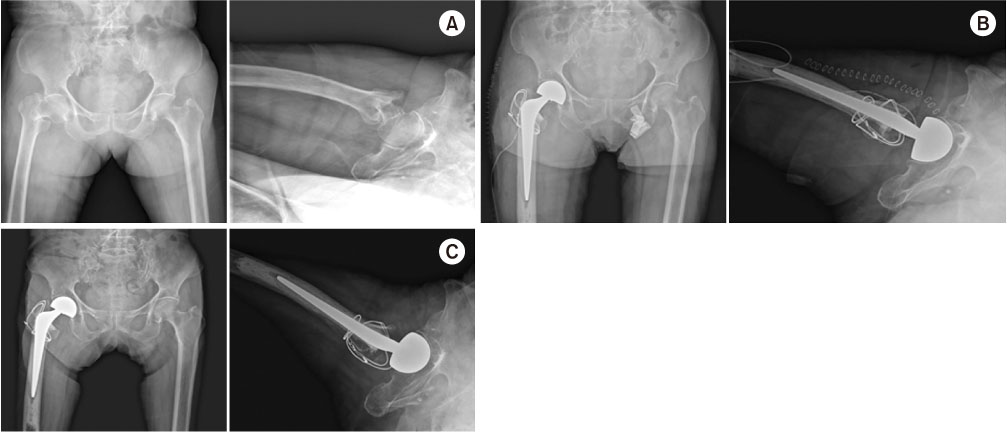

Fig. 3

A 79-year-old female with an intertrochanteric fracture underwent bipolar hemiarthroplasty. (A) Preoperatively: anteroposterior and axial view. (B) Postoperatively: anteroposterior and axial view. (C) Two-year follow-up: anteroposterior and axial view.